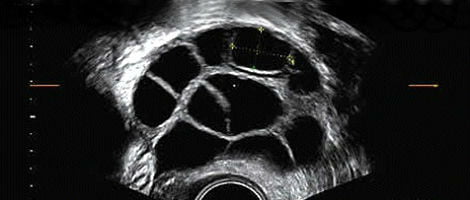

A HMG é utilizada para estimular o funcionamento do ovário. Mais especificamente, esta hormona produz um maior recrutamento de folículos e estimula o seu crescimento e desenvolvimento.

A HMG está indicada em casos de mulheres que vão submeter-se a uma técnica de reprodução assistida. A hormona é administrada através de injeções cutâneas com o objectivo de conseguir uma maior estimulação da ovulação durante o ciclo menstrual. Quando falamos da HMG estamos, na verdade, falando de uma concentração das hormonas FSH e LH em uma proporção de 50% cada uma.